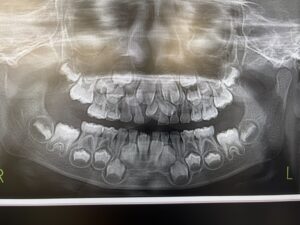

お口全体のパノラマ写真です。子供の口の中は歯がいっぱい!

因みに、この写真の中には過剰歯(余分な歯)があります。

過剰歯は、抜くことが多いですが、たまたま永久歯に障害を起こさなければ、気づかずに大人になってしまうこともあります。

歯茎の骨の中の、出来上がり途中の歯が、子供たちのこれからの長い未来を予感させてくれて、いつもパノラマ写真を見ると嬉しくなります。